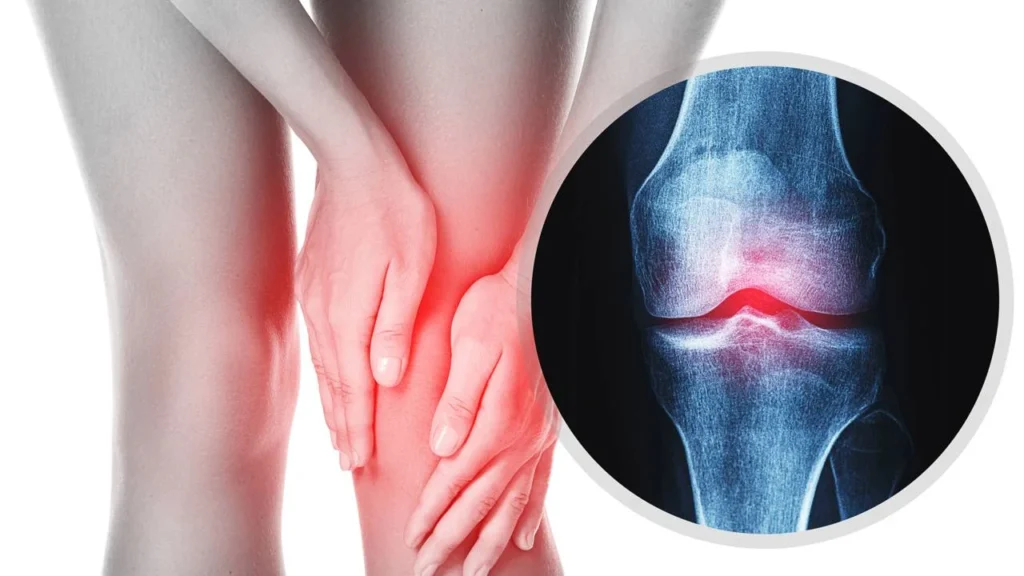

Conviver com a osteoartrite pode levar muitas pessoas a evitarem o movimento, temerosas de que a prática de exercícios possa intensificar a dor nas articulações. Entretanto, diversas pesquisas têm mostrado que a atividade física é fundamental para atenuar o desconforto e aprimorar a mobilidade, especialmente em articulações como joelhos, quadris e coluna, que são as mais afetadas por essa condição degenerativa.

O sedentarismo pode agravar os sintomas da osteoartrite. Musculatura enfraquecida aumenta a vulnerabilidade das articulações e a cartilagem não recebe a nutrição necessária, contribuindo para a inflamação. Essa situação forma um ciclo perigoso: a diminuição da atividade física gera mais dor, o que, por sua vez, resulta em ainda menos movimento.